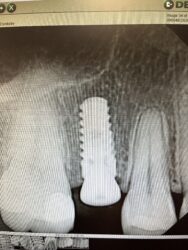

I have this case that I am preparing for. It will happen in February. I don’t have a CT on this Patient. It is a tooth that has had a RCT. I can see a PAR on tooth and caries that Fractured the crown. Tooth will come out and I am preparing for both scenarios: either extraction and socket preservation, or extraction and…

Hey Jonathan! Several different ways to attack this. If you’re thinking of potentially doing an immediate implant, I would definitely have a CBCT. If you do a lot of immediate implants, and there is sufficient bone, typically, I do these flapless

If you haven’t done any immediate implants. Typically it’s nicer to start with pre-molars as… Read more1 -